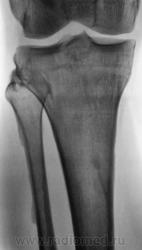

Мужчина средних лет, крепкий, ведущий активный образ жизни, занимающийся дозировано «элементами спорта», полковник милиции, в последнее время (несколько лет) почувствовал боли в области правого коленного сустава.

Снимки ниже.

Просьба высказать мнения по представленным иллюстрациям.

Энтезопатия надколенника, перегрузочная болезнь б/б кости(подозрение на неполный перелом).

Очень похожая картина на консолидированный перелом б\б кости. В проекции м\б кости определяется периостальная реакция или патологическая перестройка костной ткани.

Есть  признаки  артроза  и  синовита . Была  повреждена  передняя  крестообразная  связка.